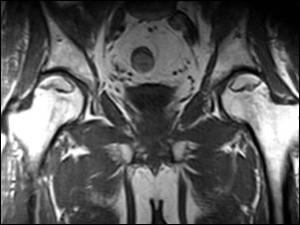

femur başı avasküler nekrozu

Femur başı avasküler nekrozu  bir sebeple( yüksek doz yada sürekli steroid kullanımı, travma) ve ya sebebi bulunamayan bir şekilde uyluk kemiğinin ( femur) baş kısmında kan dolaşımının bozulmasına bağlı kemik ölümünün gerçekleşmesidir.  Beslenmesi bozulan kemik gücünü kaybeder ve hastanın bu durumdayken ayakta dolaşması sebebiyle üzerine binen yükler sebebiyle yuvarlaklığını kaybederek çöker. Anatomik yapısı bozulan eklemde  zamanla kireçlenme (artroz) gelişir.  Femur başı avasküler nekrozu ilerleyici bir hastalıktır. Kalçada ilk başlarda hareketle artan ağrı zamanla süreklilik kazanır. Ağrı ve aksama şikâyetiyle doktora başvuran hastalarda klinik bel fıtığı ile karıştırılabilir. Hastalığın erken evrelerinde standart röntgen grafileri ile tanı konulamayabilir. İlgili hekimin hastalıktan şüphelenmesi sonucu çekilen MRI görüntüleme tanı koydurucudur. Tanı konulan hasta mutlak suretle tedavi girişimi yapılıncaya kadar etkilenen bacağı üzerine yük vermeyi azaltmalı mümkünse koltuk değneği kullanmalı ve ayakta kalma ya da spor aktivitelerinden uzak durmalıdır. Tedavi edilmeyen hastalarda hastalığın ilerleme oranı %80 ve üzeridir. Hastalığın ileri yaşlarda (50 ve üzeri) görüldüğü durumlarda total kalça protezi ile tedavi edilmesi mükemmel sonuçlar verebilir. Ancak genç hastalarda erken dönemde protez kullanılması ileride proteze bağlı gevşeme, revizyon gibi komplikasyonlar sebebiyle tercih edilmemektedir. Bu sebeple genç hastalarda eklem koruyucu tedavi yöntemleri geliştirilmiştir.